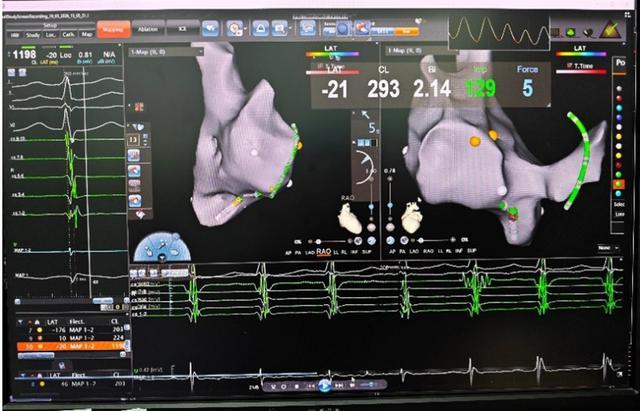

手术中,张志辉教授与罗文治主治医生凭借丰富的血管穿刺经验,精准建立手术路径。借助先进的三维电解剖标测平台,他们实时监测导管走形与头端压力,将导管顺利送入心腔。

在心腔内,无需X射线辅助,团队迅速建立三维心腔模型,精准锁定并成功消融引发心动过速的异常病灶。整台手术历时不到一小时顺利收官,全程无放射线暴露,心律失常得以根治,胎儿安全也得到了最大程度的保障。

(▲三维心腔图)

(▲成功消融病灶)